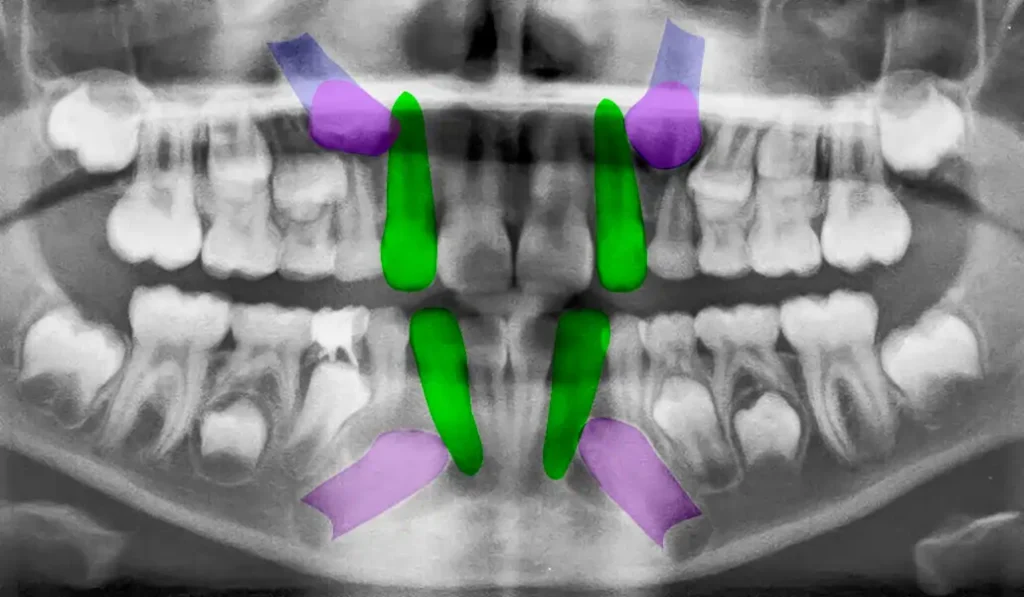

Una vez evaluada la posición y profundidad del canino retenido, se indicó su exposición quirúrgica y la adhesión inmediata del botón de tracción ortodóntica en el mismo acto operatorio. Esta secuencia permite evitar pérdidas de tiempo entre la exposición y el inicio del movimiento dentario.

La apertura quirúrgica se realizó con electrocirugía, permitiendo un campo operatorio limpio y buen control visual. Luego se instaló la mecanoterapia inicial para comenzar la rotación coronaria y orientar el canino hacia una posición más favorable dentro de la arcada.

La duración total de la intervención, incluyendo la fase quirúrgica e instalación de la mecanoterapia inicial, fue de aproximadamente 40 minutos. En el postoperatorio inmediato y mediato el paciente evolucionó favorablemente, sin dolor relevante ni complicaciones quirúrgicas.